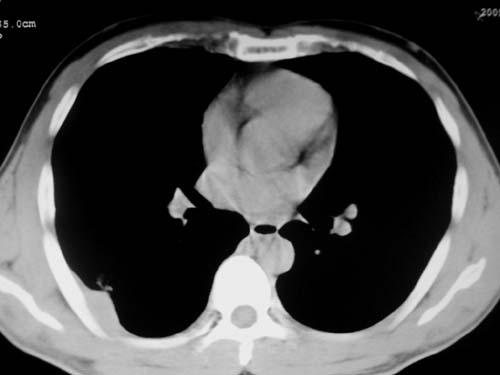

标题: CT19540: 31岁。自述结核性胸水治疗两个月后,在外院拍x线发 [打印本页]

标题: CT19540: 31岁。自述结核性胸水治疗两个月后,在外院拍x线发

右侧胸壁结节状软组织影伴相应肺叶内受侵,伴右侧胸腔积液。考虑:结核性可能大。

1、炎性病变,结核可能;2、右侧少量胸膜积液。

考虑结核性胸膜炎,胸膜肥厚,不除外胸膜间皮瘤可能,建议复查。

1)考虑右侧结核性胸膜结节。2)右侧胸膜增厚+包裹性胸腔积液。